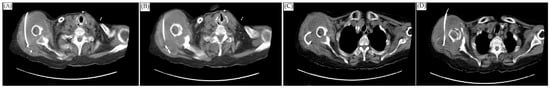

Figure 2.

CT-guided drainage of the abscess. (A,B) were the first CT-guided pigtail drainage; (C,D) were the second CT-guided pigtail drainage; the abscess of the subdeltoid space was mildly decreased. However, local swelling only mildly decreased.

The orthopedist then followed up with an MRI scan on the first day after admission and noticed a 3.3 × 8.2 cm abscess in front of the humeral head extending across subacromial and subdeltoid space with intra-articular involvement. The scan also showed a 1.7 cm inflammatory pseudotumor (IPT) within the supraspinatus muscle, and osteomyelitis of the humerus (Figure 1). The antibiotics vancomycin and ceftriaxone were prescribed upon admission. On the sixth and thirty-second days after the MRI scan, computed tomography (CT)-guided pigtail drainage was arranged, which only mildly decreased the pain and swelling (Figure 2). Because the improvement to the shoulder mass and the symptoms was rather slow, a surgical shoulder debridement procedure was arranged to remove blood clots and insert antibiotic beads. During the operation, a pulsatile tumor was noticed. The orthopedist did not complete the tumor resection or tumor biopsy for the risk of tumor rupture combining uncontrolled bleeding. Under the impression it was a pseudoaneurysm, the orthopedist team decided to complete the debridement without touching it.